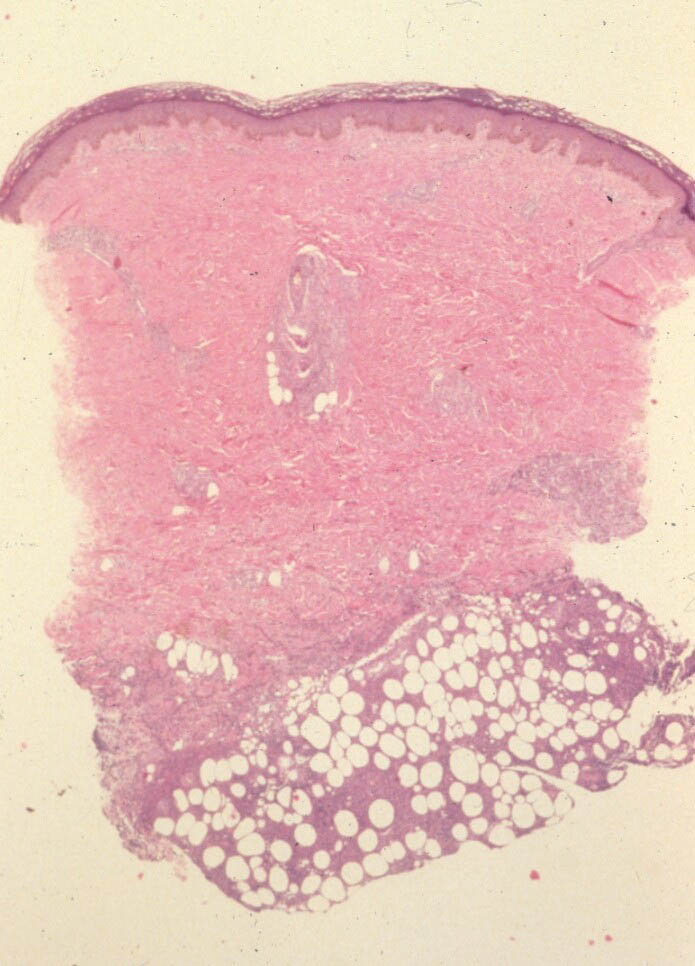

Atlas of skin histopathology

Panniculitis = التهاب السبلة الشحمية